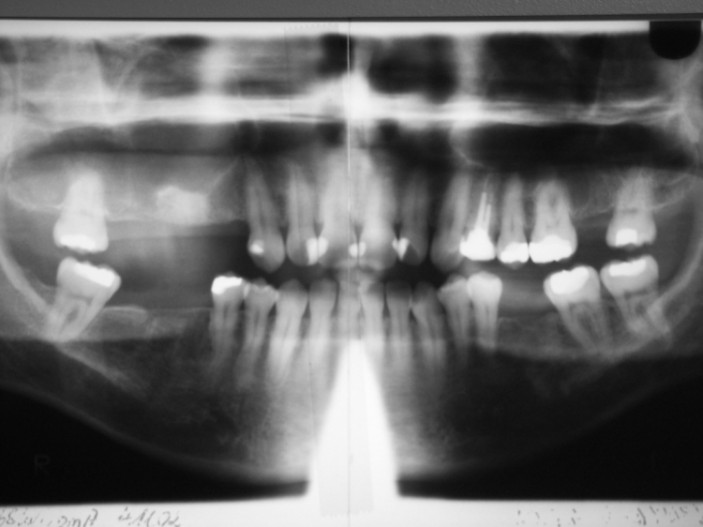

Da eine ausreichende Compliance seitens der Patientin als gesichert angesehen werden konnte, erfolgte zu diesem Zeitpunkt die Planung für die komplette Restauration des stark geschädigten Gebisses. Neben mehreren aufwendigen Extraktionen und Osteotomien der zerstörten Zähne erfolgte die Etablierung einer adäquaten Mundhygiene durch ein entsprechendes Prophylaxeprogramm. Die mit der Patientin vereinbarten Termine wurden von ihr konsequent eingehalten. Aufgrund starker beruflicher Beanspruchung umfasste die Vorbehandlung den Zeitraum eines Jahres (Abb. 2). An einer inzwischen völlig angstfreien Patientin konnte nun die abschließende prothetische Therapie vorgenommen werden. Insgesamt wurden zwei Brücken und eine Krone zur Wiederherstellung der Funktion und der Ästhetik eingegliedert (Abb. 3). Seit Abschluss der Gesamtsanierung befindet sich die Patientin im permanenten Recall zum langfristigen Erhalt des erreichten Zustandes.